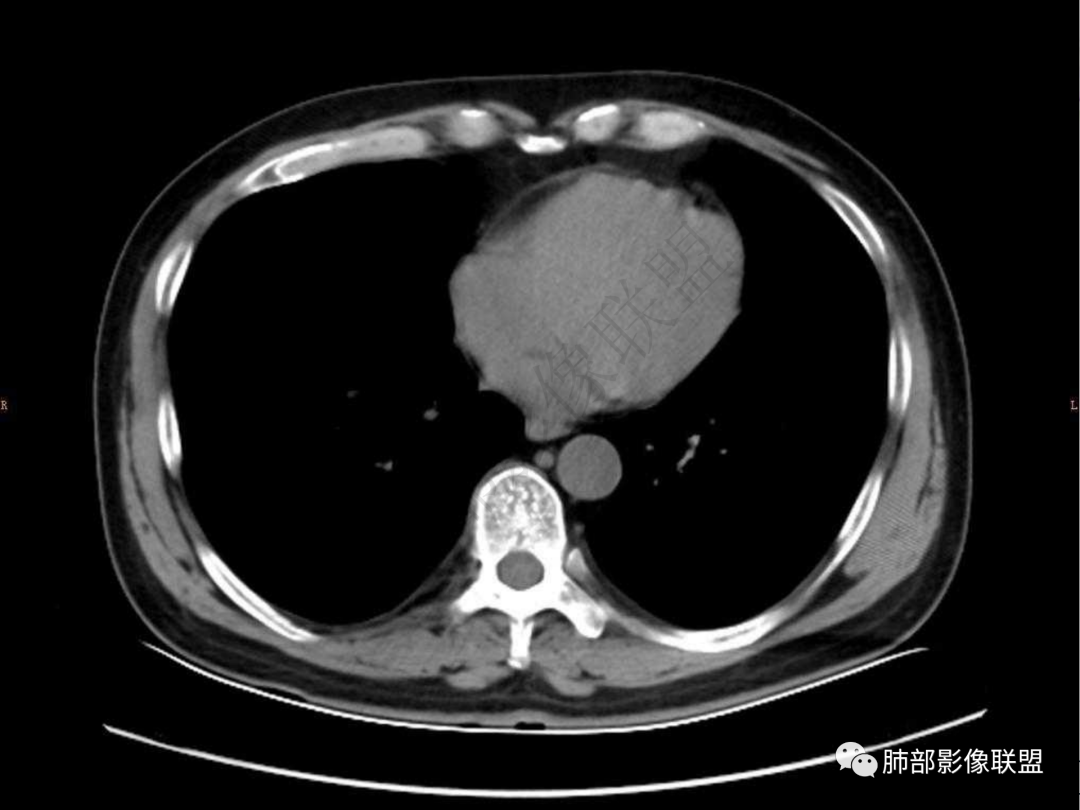

4.实性部分不均匀环形强化并显示一小范围低密度坏死区或空洞。较之肺窗,整体纵隔窗范围较小,提示病灶并不十分密实。抑或为不同时段图像。

5.双肺门及纵隔未见增大淋巴结。未见胸腔积液。

肺脓肿:环形强化,强化较显著。如出现明显囊壁样强化甚至边缘“憩室”样突出,高度支持肺脓肿。